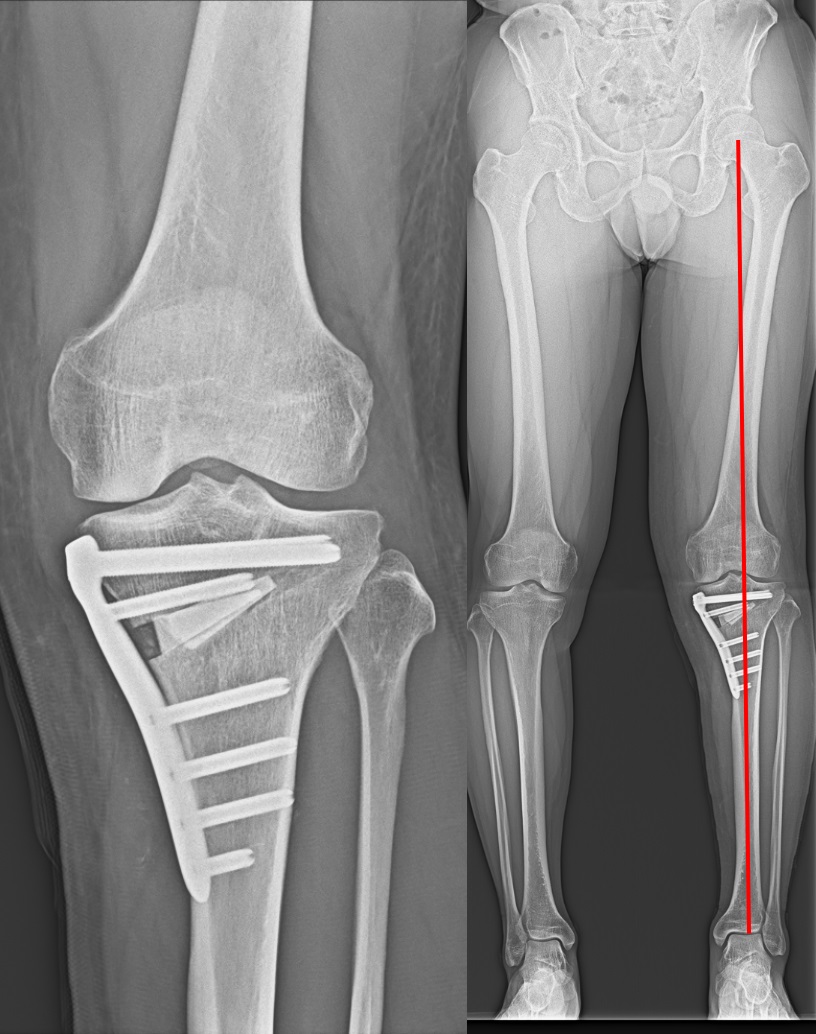

高位脛骨骨切り術(high tibial osteotomy: HTO)

初期の変形性膝関節症や大腿骨顆骨壊死などに適応があります。

O脚変形のために内側に偏った荷重線を、自分の骨を骨折させ角度を変えることにより、比較的きれいな軟骨の存在する外側に荷重線を移動させる手術です。荷重線が移動することによって膝の痛みが緩和されます。

膝関節そのものは温存されるため、人工膝関節置換術では困難な正座やスポーツ活動へ復帰された患者さんが多くいらっしゃいます。